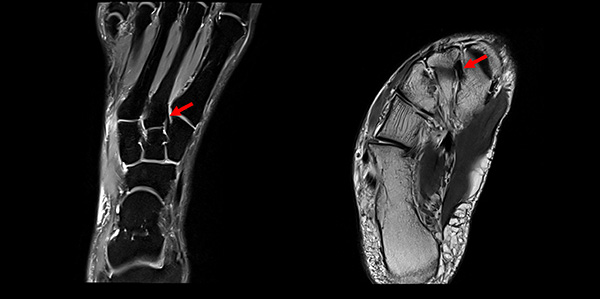

Das Lisfranc-Ligament selbst lässt sich am Besten im MRT beurteilen. Gelegentlich lässt sich im MRT ein Knochenmarksödem als einziges Zeichen einer nicht dislozierten Fraktur finden. Die MRT-Diagnostik ist allerdings eher unklaren interossären Erweiterungen bei persistierenden Schmerzen zur Suche nach isolierten Bandverletzungen vorbehalten 7511.

Zum Lesen der Bildbeschreibung und zur Vollansicht bitte das Bild anklicken.